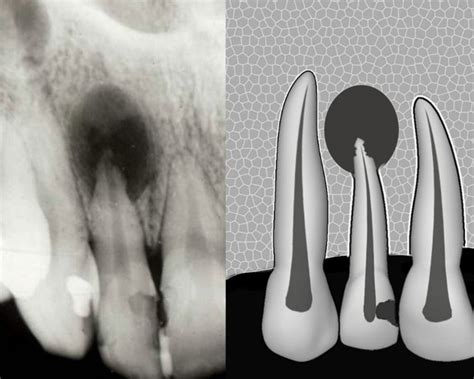

Un paciente de 58 años acudió solicitando asesoramiento en relación con un posible tratamiento protésico. En la radiografía panorámica practicada, se descubrió casualmente una imagen radiolúcida interradicular clínicamente asintomática en las regiones 11 y 21 con unas medidas aproximadas de 11,9 x 7,7 mm.

Quiste radicular con origen en el diente 21.

En la tomografía se observó una masa circunscrita interradicular palatina de 7,0 x 4,9 x 6,4 mm en las regiones 11 y 21 que comunicaba con la fosa nasal izquierda (2,2 x 14,6 mm). En base a estos resultados se estableció el diagnóstico de sospecha de un agujero incisivo ensanchado. Las raíces de los dientes 11 y 21 limitaban con la masa. En la zona apical, las raíces mostraban una divergencia hacia distal y el paciente presentaba un ligero diastema medial y también diastemas laterales.

Se informó al paciente del resultado de la tomografía, el cual carecía de importancia para el tratamiento previsto. Se recomendó al paciente llevar a cabo el tratamiento protésico de los dientes que precisaban ser rehabilitados. Se le recomendó asimismo que acudiera nuevamente al centro lo antes posible en caso de aparición de síntomas clínicos.